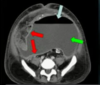

1. VEIA MESENTÉRICA

2.ARTÉRIA MESENTÉRICA

3. VEIA RENAL.